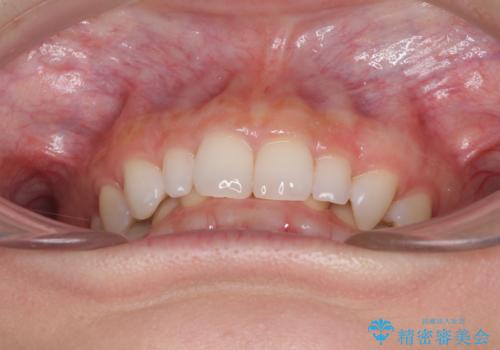

前歯のデコボコと小さい歯を改善 インビザラインとオールセラミッククラウン

- 前歯のデコボコと左右の矮小歯を気にして来院された患者様です。

矮小歯の前後にスペースを作るようにインビザライン矯正治療を計画し、矯正治療後にオールセラミッククラウンによる補綴治療を行うこととしました。

何とか矮小歯を改善するスペースを作ることはできましたが、過蓋咬合を改善するには至りませんでした。